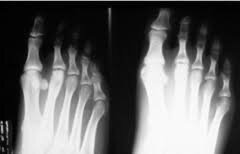

• Sistema Radiográfico de Levinshon.

Sistema Radiográfico de Levinshon.

El Profesor Levinshon creó el Sistema Radiográfico que consiste en la medición efectuada sobre radiografías, que se obtienen de las falanges del metacarpo y del metatarso. Tiene el inconveniente que no se aplica en personas que atraviesan etapas de crecimiento, en menores de edad y presenta el inconveniente que el material que se emplea es excesivamente costoso.